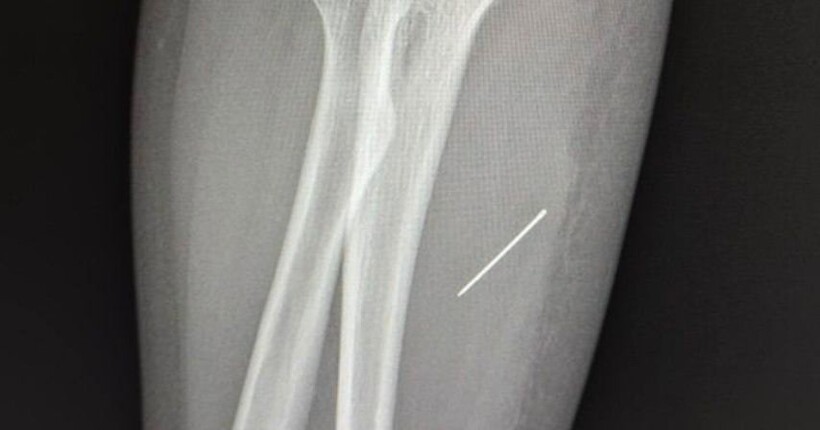

Під час обстеження дівчини медики запідозрили наявність стороннього тіла. Під час УЗД лікарі виявили у руці дівчинки - голку.

Рентген показав, що вона зайшла під кутом близько 45 градусів і застрягла в товщі м’язової тканини. Подальша міграція предмета могла призвести до ушкодження судин або нервових закінчень потерпілої.

Під час операції лікарі витягли голку точно по траєкторії її входження, щоб уникнути ламання.